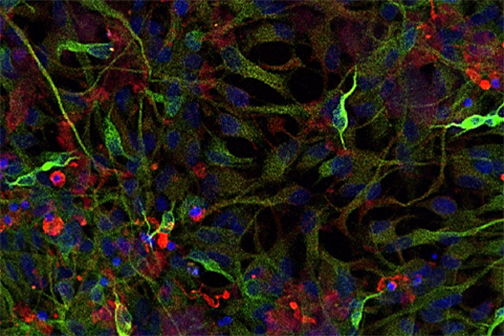

LSU Health New Orleans Develops New Human Cell Line to Study Blinding Eye Disorders

Under the direction of Boyd Professor Nicolas Bazan, MD, PhD, scientists at LSU Health New Orleans Neuroscience Center of Excellence have developed a new, experimental human cell line from retinal pigment epithelial cells. Called ABC, these cells so closely resemble and retain the properties of native retinal pigment epithelial (RPE) cells, the research team has shown that they are a reliable cell system to study retinal degenerative diseases. More